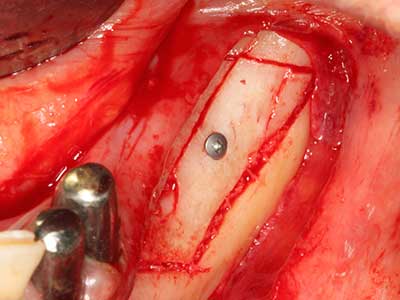

Fig. 21: Extended maxillary anterior-tooth defect with indication for distraction osteogenesis with scar tissue after prior operation.

Fig. 22: The mobile segment can be precisely separated with the thin osteotomy saw (W&H Piezomed).

Fig. 23: Final mobilization of the palatally branched distraction segment with the chisel.

Fig. 24: Application of the distractor (TRACK-System, KLS Martin).